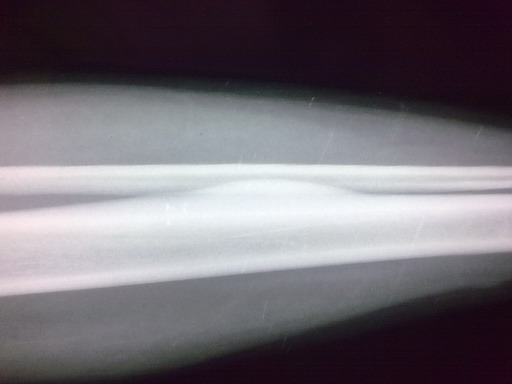

女孩,14岁,小腿疼痛一周,局部隆起,质硬,无红肿热痛

胫骨骨干皮质梭形增厚,虽无瘤巢,也考虑骨样骨瘤,原因不明,可能与感染有关,服用水杨酸制剂看看。

左胫骨中段内前方骨皮质梭形增厚,髓腔未见累及,无骨膜反应。考虑良性病变。我考虑1低毒感染。

2骨样骨瘤:骨硬化较重,可能包埋了“瘤巢”。不象的地方就是病史不太支持:病程比较短,症状比较轻。试服用水杨酸制剂看看。

考虑骨样骨瘤。病灶内部结构显示不清,请调调ct窗宽窗位。